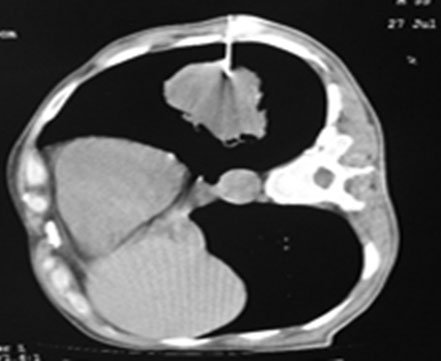

CT guided lung biopsy

Procedure in which 2 or 3 small pieces of tissue are taken with help of fine needle or biopsy needle under ultrasound guidance or CT guidance and local anaesthesia.